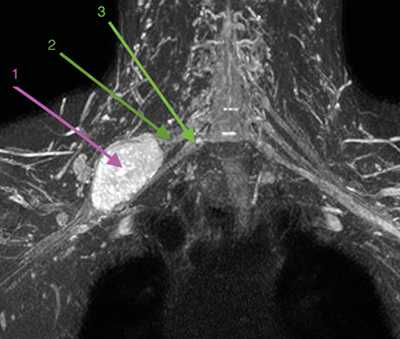

Con la orientación diagnóstica inicial de schwannoma de plexo braquial derecho con escasa repercusión clínica, se decidió actitud expectante. Se instauró tratamiento analgésico de primer escalón y ansiólisis a demanda para dormir. El paciente era reticente al tratamiento neuromodulador debido a sus efectos secundarios. Seis meses después, tras una nueva RM de control, se observó un discreto crecimiento de la lesión con probable efecto compresivo por los músculos escalenos anterior y medio (Figuras 1 y 2). Se indicó una infiltración diagnóstico-terapéutica con toxina botulínica tipo A (Botox®) ecodirigida. Las crisis de dolor eran más frecuentes y de más minutos de duración y empezaban a afectar su calidad de vida. EVA 2-3 en reposo, 8-9/10 en las crisis.

Fig. 2. RM coronal en STIR. 1. Schwannoma de plexo braquial derecho. 2. Tronco medio del plexo braquial. 3. Tronco inferior del plexo braquial